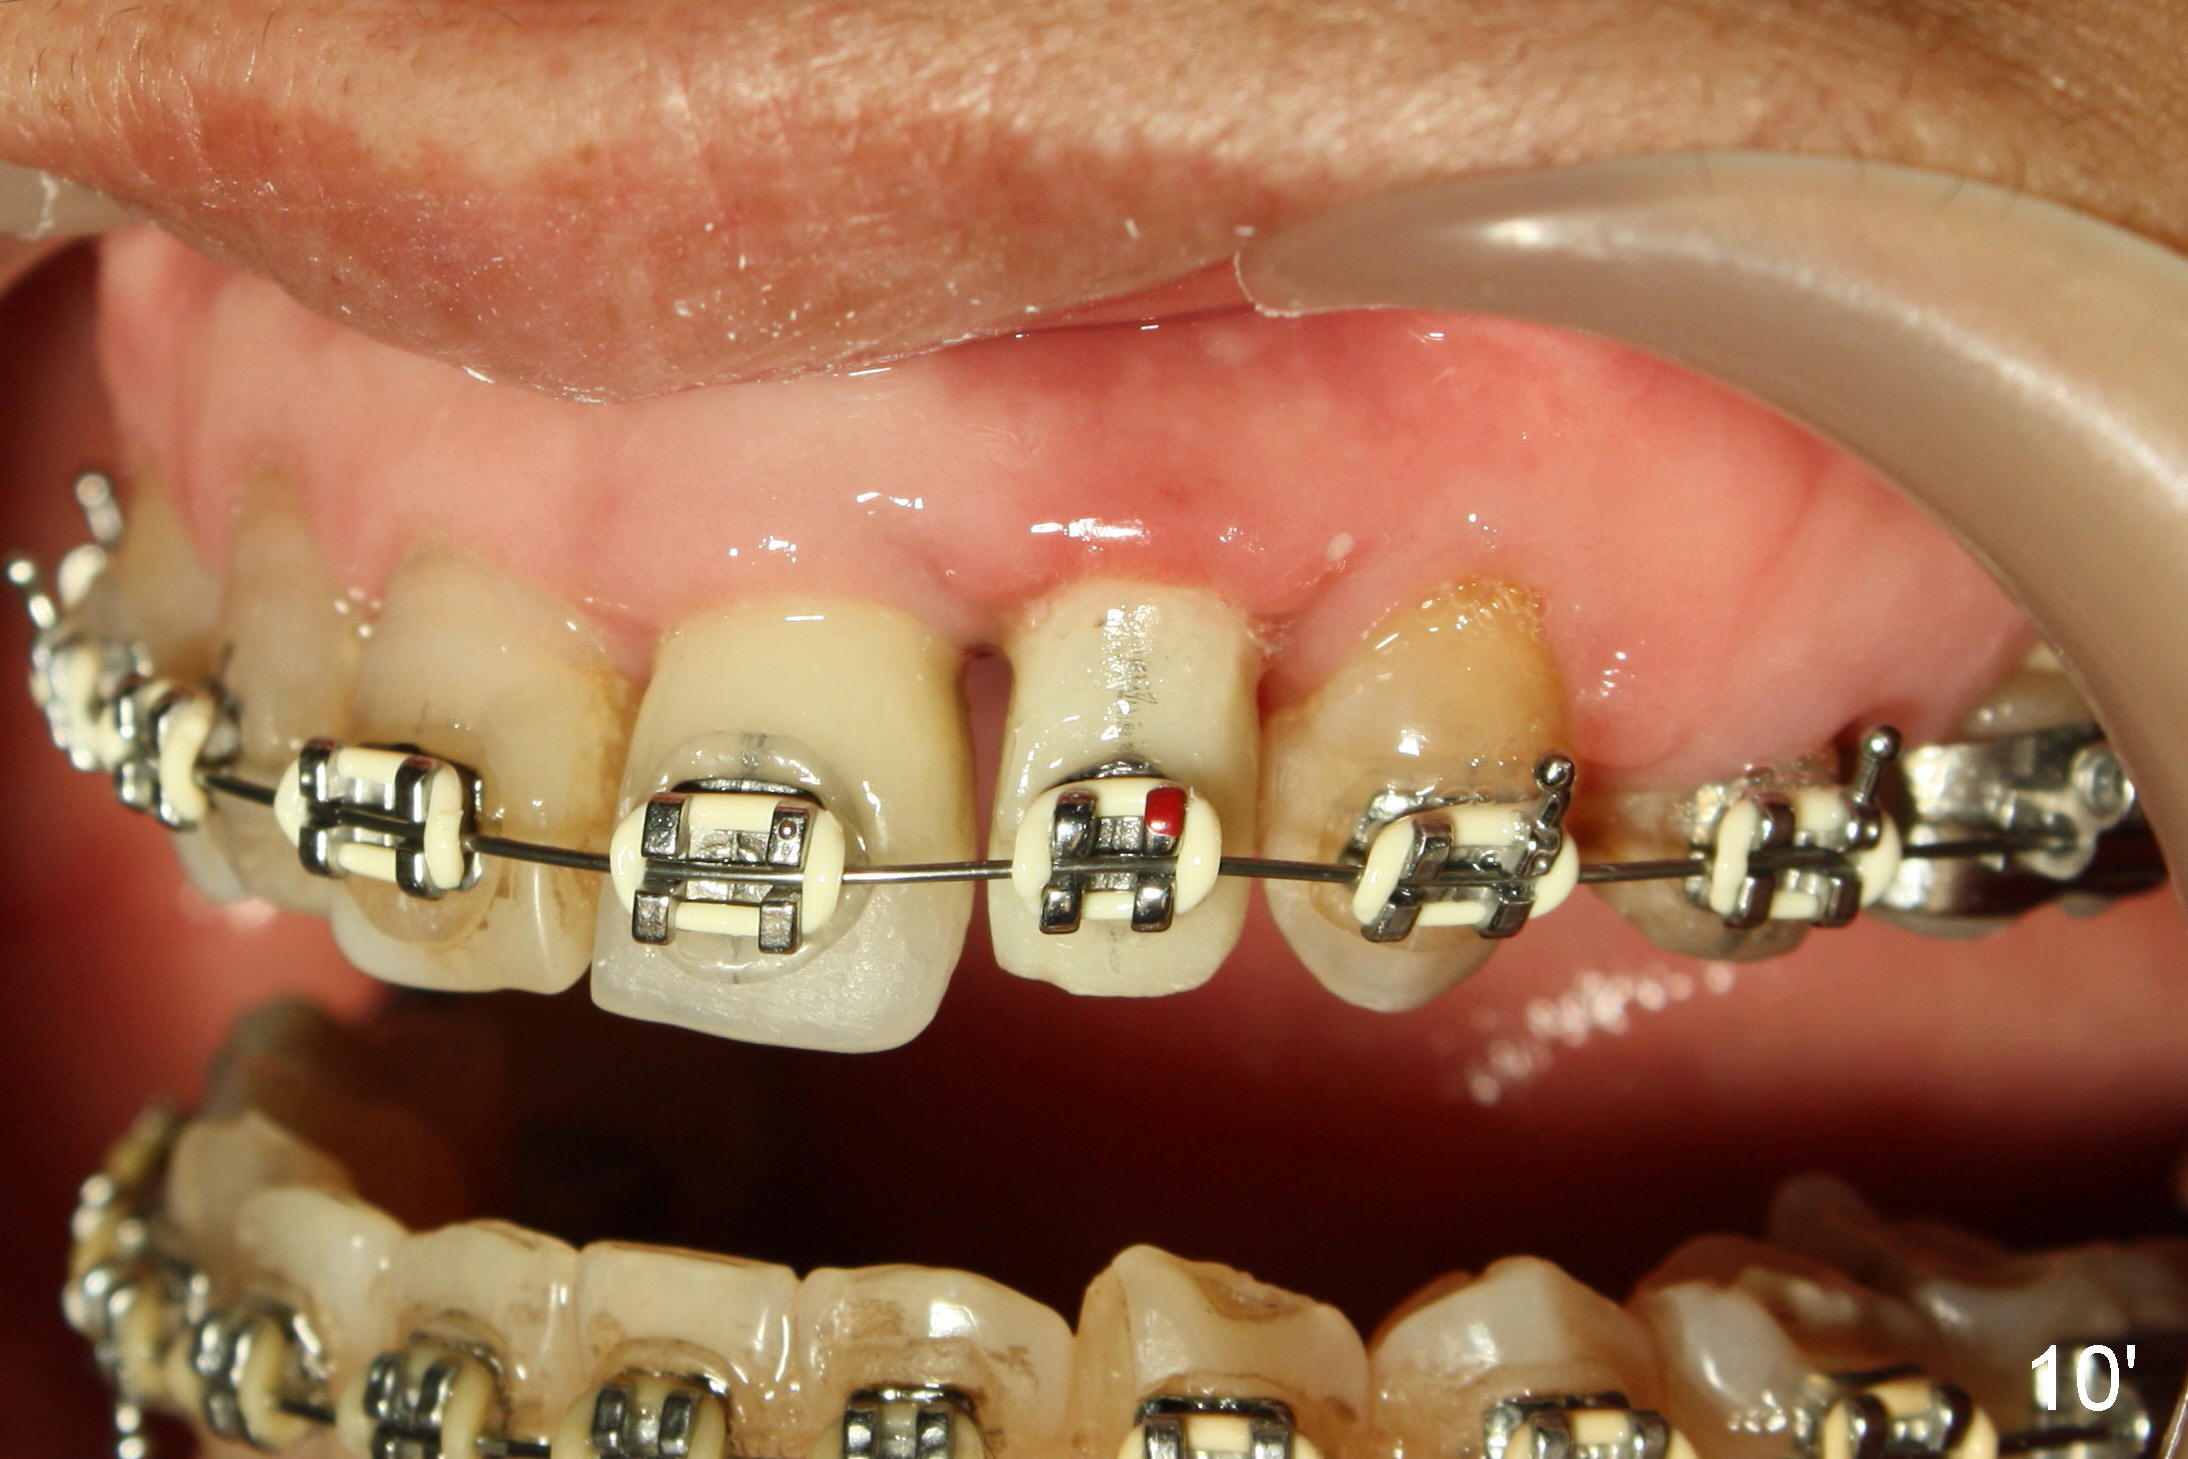

A prominent feature of implant failure in this case is pain. The patient feels that the pain is from the base of the nose. PA taken 3 days postop shows that the implant is inferior to the nasal floor (Fig.2 red ^). Clinically, the buccal gingiva continues to be erythematous 10 days postop (Fig.1). The pain is so unbearable that the implant (3.8x14 mm) is removed 10 days post placement. After repeated debridement, a 4.1 mm tap (Fig.3 T) is manually inserted with torque. A 4.1x14 mm submerged implant is placed with insertion torque < 30 Ncm, but it is placed subcrestally (Fig.4 <--). This time an immediate provisional is not provided. The flap is sutured. The pain disappears immediately. No infection is found 7 days postop (Fig.5). However, an asymptomatic vesicle is noted at the crest 3 weeks postop (Fig.6). The gingiva looks normal 2 and 3 months postop (Fig.7,8). The coronal gap dissolves 3 months postop (Fig.9 >, as compared to Fig.4), suggesting osteointegration. The implant is uncovered 4 months postop (Fig.10). Bracket is placed 5 months postop (Fig.10'). One month later, the left central incisor improves in position coronocervically (Fig.11), but the overjet needs correction by distalization of the upper anterior teeth. The implant at the site of #10 may be used as an anchorage.